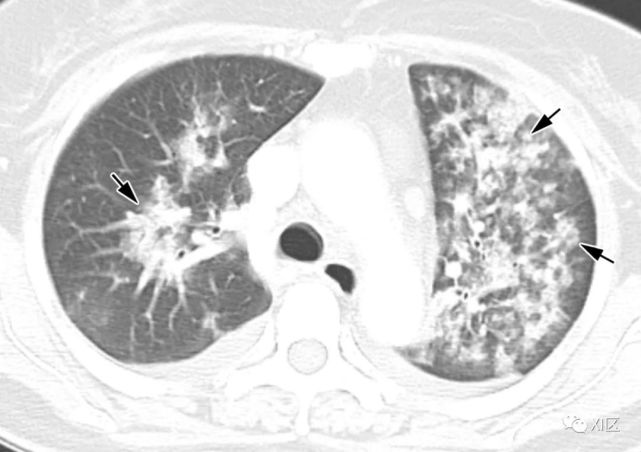

图7 甲型流感病毒引起的肺炎表现为沿支气管血管束的多个不规则的实变区(箭)和弥漫性GGO(箭头),两肺小叶间隔增厚。

图14 一位22岁女性感染前1个月因急性淋巴细胞白血病接受单倍体相合骨髓移植治疗,有发热,诊断为 HPIV病毒性肺炎。

在主支气管水平(上)和叶间区水平(中上)的初始轴位胸部CT图像显示沿支气管血管束和轻度支气管壁增厚(箭头)的多灶性不明确结节性GGO病变(箭)。中性粒细胞减少持续存在。(中下,下)随访10天后获得的轴位胸部CT图像显示病变的范围和强度增加,并沿支气管血管束增加不规则的实变结节(箭)。尽管进行了重症监护,该患者仍然死亡。